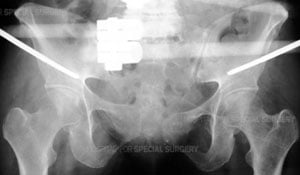

Radiograph of the pelvis demonstrating application of a pelvic external fixator.

Patients with pelvic fractures may require one or more surgical procedures. The surgeon may begin with an External Fixation (Ex-Fix) technique in which an open or closed reduction is performed and the bones are then held in place using an external fixator, or frame. This is done by threading pins into the bone on either side of the fracture. These pins are then connected to rods outside the skin, which form a frame.